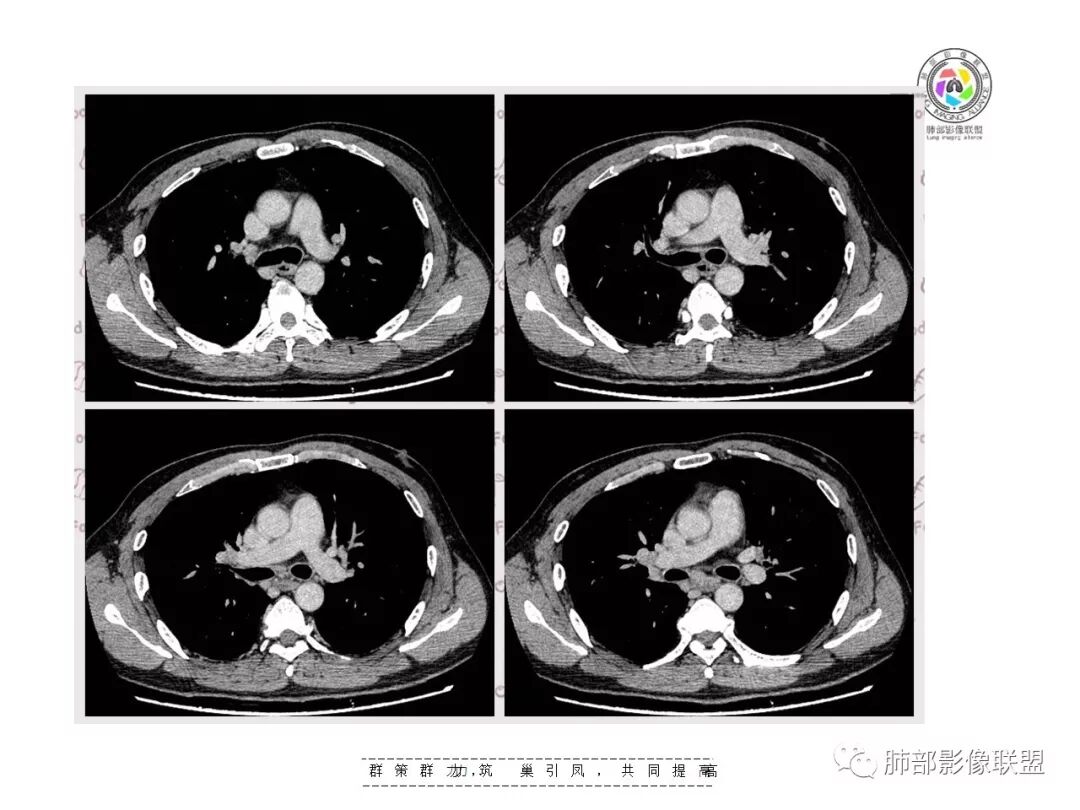

【影像资料】

但是问题来了:淋巴结

南边:

右肺门区淋巴结增大,融合,密度均匀,均匀强化

符合这个特点的:结核?淋巴瘤?转移瘤?

淋巴结我觉得目前的特点:淋巴瘤?结核?

王秀仙东宁市第二人民医院影像科:晨读:右肺下叶实变及磨玻璃影,边缘有收缩有膨隆,部分支气管进入扭曲扩张,磨玻璃影边缘清晰,实变影明显强化,内可见血管造影征,纵膈及肺门淋巴结肿大并强化,考虑粘液腺癌。

登封市三康医院(刘权威):右下肺肺不张,磨玻璃影,边缘清楚,空气支气管征,增强有强化,纵膈及右肺门淋巴结肿大并强化,考虑恶性肿瘤,粘液腺癌可能。